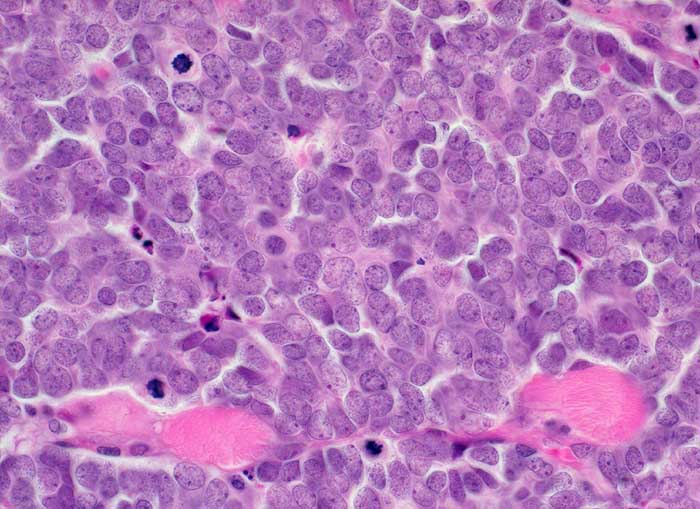

Merkel Zell Karzinom

Solides sehr monomorphes Tumorzellinfiltrat. Die Tumorzellen haben praktisch kein Zytoplasma. Das Chromatin ist fein granuliert. Die Kerne enthalten feine Nukleolen. Zahlreiche Mitosen. Der Tumor infiltriert die Skelettmuskulatur.

Immunhistochemie: CK20 und Synaptophysin positiv. Melanommarker, CD20, CD45, TTF1 negativ.

Tumor am Unterlid

Histologie

400